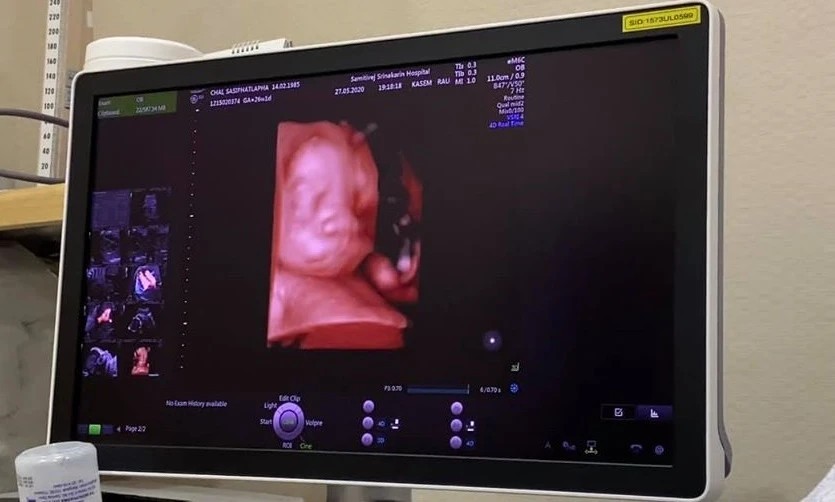

การตรวจอัลตราซาวนด์ ในสตรีตั้งครรภ์

การตรวจอัลตร้าซาวด์เมื่อตั้งครรภ์ จำเป็นหรือไม่ มีอันตรายต่อลูกในครรภ์หรือไม่ และเมื่อตรวจแล้วจะสามารถรู้อะไรได้บ้าง ที่นี่มีคำตอบค่ะ